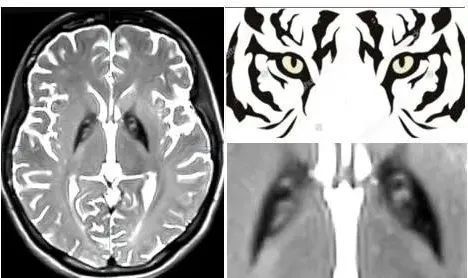

在完善头颅磁共振后,中山一院神经外科团队发现苗苗的双侧基底节区的苍白球内侧部存在可疑“虎眼征”。“我们考虑患者可能是遗传代谢性疾病,建议完善基因检查并采取了对症治疗措施。”神经外科副主任刘金龙教授说。

头颅磁共振成像,出现形似老虎眼睛

基因检查后很快给出了结果。刘金龙说,苗苗的PANK2基因纯合突变,结合临床表现及基因检测结果,最终确诊她是原发性遗传性肌张力障碍,类型为泛酸激酶相关神经变性病。